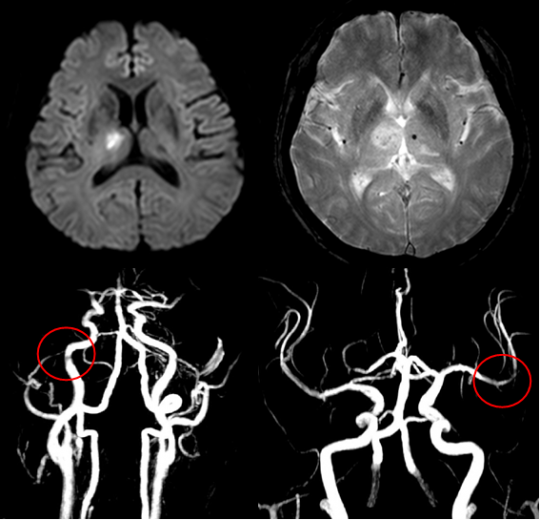

뇌경색에는 두 가지 주요 유형이 있습니다. 첫 번째는 허혈성 뇌경색으로, 대개 혈전이 혈관을 막아 발생합니다. 두 번째는 출혈성 뇌경색으로, 뇌혈관이 파열되거나 약해져 출혈이 발생하는 것입니다. 본 포스팅에서는 주로 허혈성 뇌경색의 초기 증상에 대해 설명드리겠습니다.